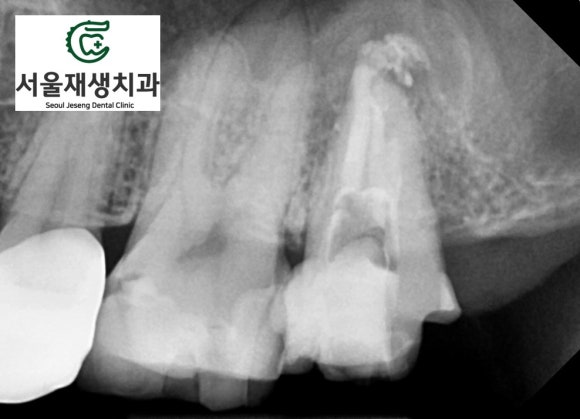

한 달 정도 경과했을때...

통증도 없으시고 치아 내부도 깨끗해졌습니다.

한 달 반정도 되었을 때...

뿌리 끝의 염증의 크기가 확연히 감소한 것처럼 보입니다.

CT를 찍어서 정확히 비교해봅니다.

뿌리를 타고 상악동까지 넘어가 있던

염증이 모두 사라졌습니다.

심지어 뿌리 주위로 새로운 골이 자라들어오는 소견입니다.

한 달 반만의 일입니다.

이렇게까지 빨리 아물길 바란 건 아니었는데....

무서운 회복력을 가지신 환자분입니다.